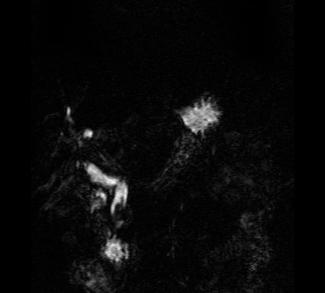

These are both MR images. The image on the left is a coronal T2-weighted sequence, with bright fat and high signal fluid in the stomach and biliary system. The image on the right is a 3D reconstruction that just shows the biliary system, an MRCP. Both studies show a dilated biliary tree and a low signal lesion in the distal CBD consistent with a stone. MR is usually not the first study done in patients with jaundice, but can be very useful in complex cases where US or CT do not give a clear diagnosis.